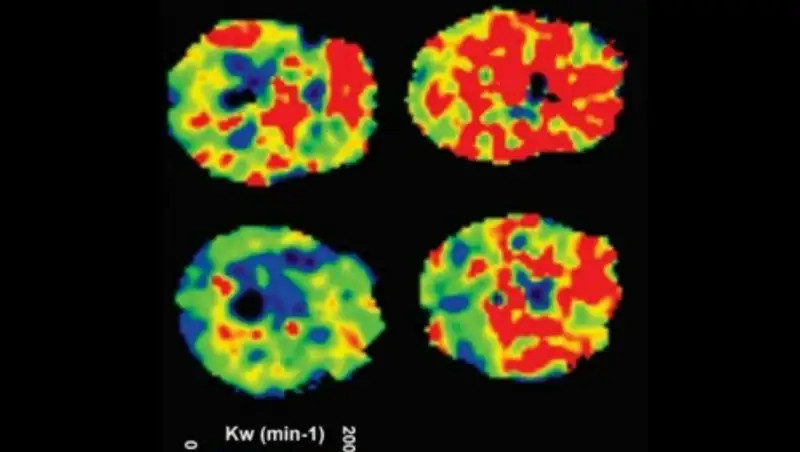

Американские ученые оценили влияние двух типов сахара на метаболизм и сосуды. Они провели эксперимент на самках крыс. Грызуны получали с пищей раствор глюкозы (продукта расщепления углеводов) либо фруктозы, которая содержится во фруктах и фруктовых соках. Растворы крысам давали в течение восьми недель, что эквивалентно шести годам жизни человека.

Контрольная группа грызунов пила обычную питьевую воду. Исследование показало, что обе группы, которым давали растворы, потребляли больше калорий по сравнению с контрольной группой. Общий уровень потребления калорий был выше в группе грызунов, получавших раствор глюкозы.

Несмотря на это, масса тела существенно увеличилась только у крыс, которым давали раствор фруктозы. Кроме того, у этих грызунов заметно повысился уровень триглицеридов, увеличился вес печени, а также сжигалось меньше жира в печени. Еще крысы, получавшие фруктозу, были склонны к проблемам с кровяным давлением.